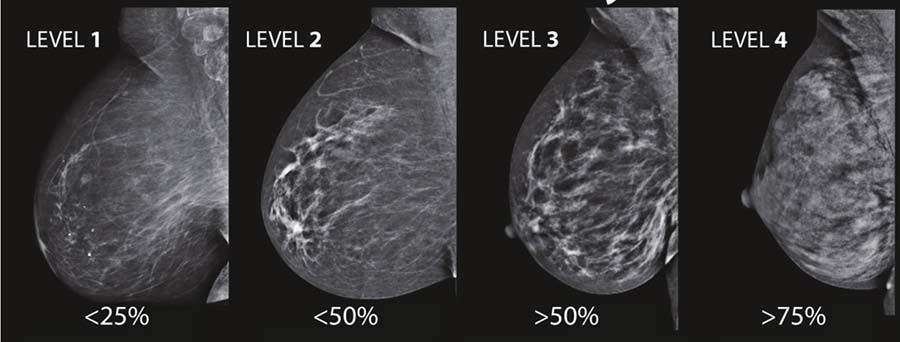

年轻女性的乳腺腺体往往更致密,这不是摸起来的感觉,而是指医学影像中的特征。往往脂肪越少、腺体越多的乳房,致密度越高。

图源:《她说:菠萝解密乳腺癌》

在上图中,从左到右乳腺致密程度依次增加。在X光下脂肪是暗色且微微透明的,所以肿瘤组织(呈亮白色)就可以较容易被发现。而致密性乳房中的腺体和纤维组织很多,因为它们也呈白色,肿瘤容易“隐藏”在里面,就像一只兔子藏在枝干和绿叶密集分布的丛林里一样。

这也导致了许多年轻的觅友错过了早期干预的机会,确诊时病情就已经进展了。因此,对于年轻的乳腺癌患者(《中国年轻乳腺癌诊疗专家共识》将其定义为40岁之前),钼靶+超声是更保险的选择!